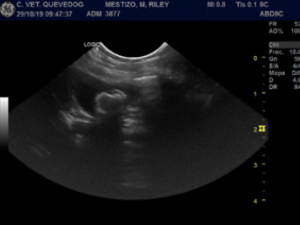

La colelitiasis es una enfermedad poco común en los perros. Los signos clínicos suelen ser inespecíficos y la frecuencia de colelitiasis sintomática es baja. Sin embargo, si evoluciona puede provocar una obstrucción biliar extrahepática con consecuencias sistémicas graves. Se presentó un Spaniel Japonés de 11 años por aparentes episodios recurrentes de dolor abdominal agudo con 1 semana de duración. 3 meses antes fue dado de alta por un episodio de colecistitis manejado con tratamiento conservador.

Se realizaron varias pruebas laboratoriales (hemograma, bioquímica y urianálisis) y tras un estudio ecográfico abdominal se observaron varios colecistolitos. Se realizó una colecistectomía por laparotomía convencional y se verificó la permeabilidad del conducto cístico y colédoco mediante cateterización y flushing normógrados. No hubo complicaciones intraquirúrgicas y el dolor abdominal se resolvió completamente. En este caso, se consiguió la resolución completa de la sintomatología patológica derivada de la presencia de colelitos biliares mediante una corrección quirúrgica electiva y temprana.